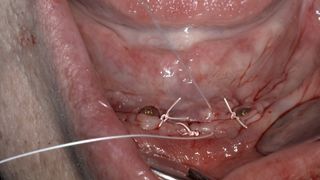

Implant surgery is similar to many other oral surgical procedures. It starts with appropriate preparation for the surgery. Like in other oral sur­gical interventions, working under sterile conditions is mandatory. Im­plant placement normally requires raising a soft tissue flap, preparing the implant beds by drilling the alveolar bone, placement of the im­plants and healing components, fol­lowed by adequate closure of the wound.

Know how to assess bone quality, perform an appropriate incision to raise a full-thickness flap and expose the bone.